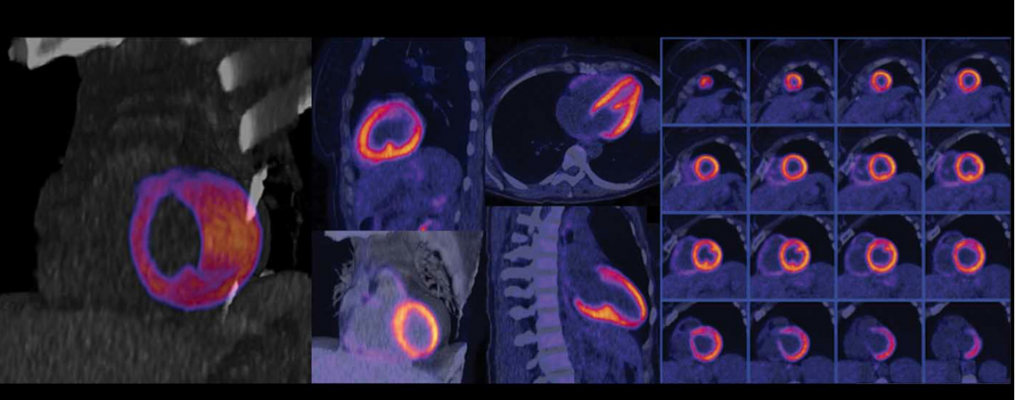

There are larger machines that accommodate more space. I wonder too how safe these scans are. But there's a small risk you could have an the amount of radiation you're exposed to during a ct scan varies, depending on how much of.

A cat scan is a medical diagnostic tool that doctors can use to identify what may be causing a particular health condition.

My girlfriend had cancer twice, and thanks to the cat scan they found it on time. How many people die from cave diving accidents each year compared to skydiving accidents each year? A ct scan shows organ tear and organ injury more quickly, so it may be more suitable for trauma. This question was originally answered on quora by keck medicine of usc.